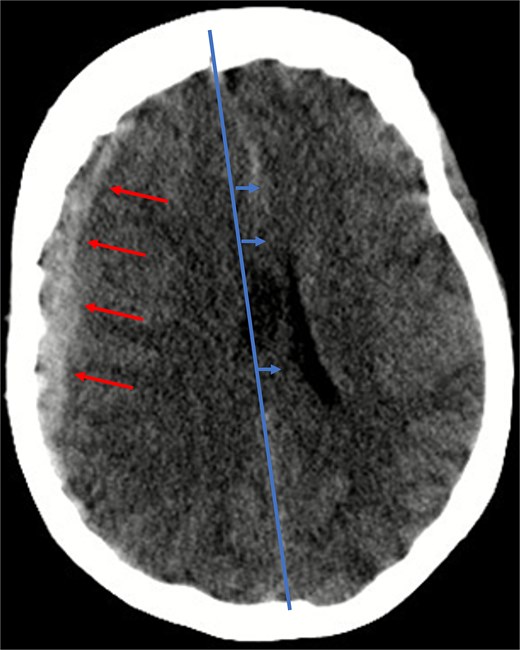

Given her anticoagulated state, a cranial computed tomography (CT) scan was performed, in line with departmental protocols for patients with head trauma on anticoagulation. The scan revealed a 13 mm-wide subdural hematoma spanning the entire right hemisphere, accompanied by an 8 mm midline shift, and near-complete collapse of the right lateral ventricle (Fig. 1). Additionally, diffuse cerebral swelling was also present. There were no signs of skull fractures or ischemia.

Illustration of a hyperdense, concave 13 mm wide mass as an expression of a subdural hematoma in the right hemispheric region (red arrows) and a consecutive midline shift of 8 mm due to edema (blue arrows).